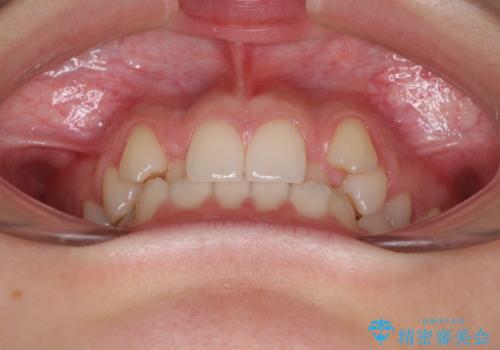

目立つ八重歯を目立たない装置で ハーフリンガルによる抜歯矯正

- 前歯のデコボコと八重歯を気にして来院された患者様です。

目立たない装置を希望されたので、上顎が裏側装置のハーフリンガルを選択し、左右上顎小臼歯1本ずつを抜歯して、矯正治療を行うこととしました。